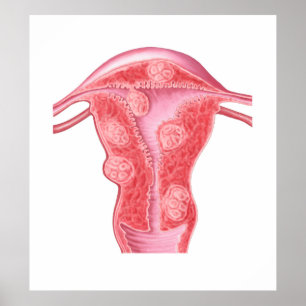

Poster Opiniões de um feto na mulher,Ob-Gyn Medical

Preço151,00 €